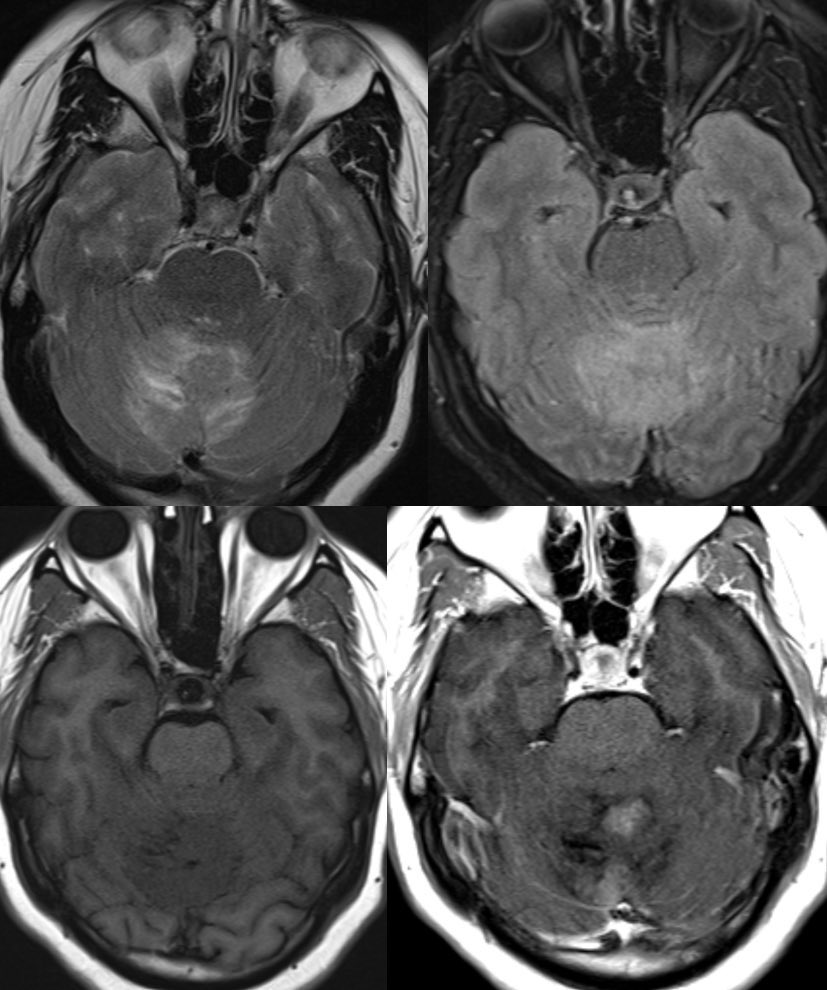

▶️Subgroup sonic hedgehog: ~30% of medulloblastomas

▶️Arise from granule cell precursors to FORM THE CEREBELLAR CORTEX (why SHH subgroup often looks cortically based in the cerebellum)

🔷Epidemiology: Bimodal age distribution of infants and adults w/ slight M predominance

🔷Prognosis is intermediate though worsened by associated MYCN or TP53 mutations

🔷Location: Most commonly LATERALLY IN THE CEREBELLAR HEMISPHERES (~62%)

🔷Predicting subgroup by LOCATION (not exclusive):

1️⃣Cerebellar peduncle/CP angle cistem: Wingless (WNT)

2️⃣Cerebellar hemispheres (lateral): Sonic Hedgehog (SHH)

3️⃣Midline/intraventricular: Predominantly but not exclusively groups 3 and 4

🔷Imaging:

💡 Hypercellular tumor so DENSE on CT and DIFFUSION RESTRICTION (consistent feature)

▶️Round/lobulated morphology

▶️Hemorrhage is rare but calcifications seen in ~20%

💡 Most medulloblastomas enhance except group 4 which may have minimal to no enhancement

⭐️ Companion case of Lhermitte-Duclos - Unilateral cerebellar mass w/ striations due to hyperintense expanded fovea on T2 w/ normal signal intervening parenchyma

💡 Both Lhermitte-Duclos & Medulloblastoma SHH can have a striated appearance! Use DWI/ADC, density on CT, & enhancement to distinguish!